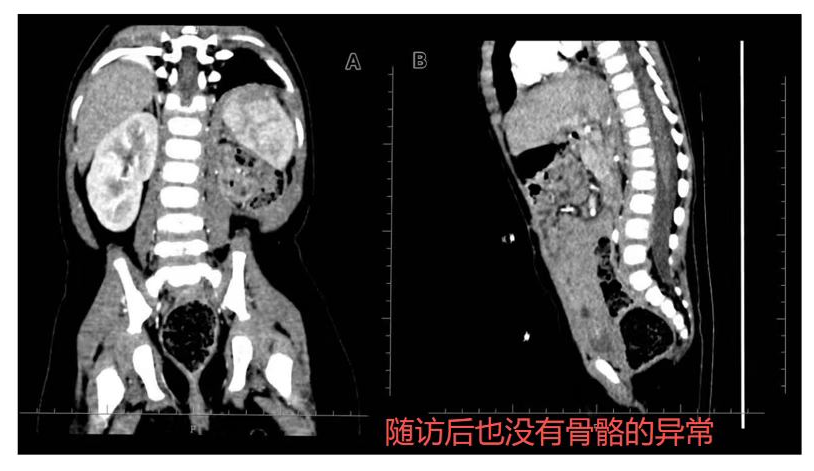

“此外,团队在治疗过程中针对脊柱及生长板的精准照射做了充分优化。通过剂量学优化设计,显著降低了脊柱和生长板的辐射剂量,确保了在治疗后1年的随访中,患儿未见明显的脊柱侧弯或生长抑制。”

值得高兴的是,经过1年的随访,患儿无肿瘤复发,肾功能和肝功能持续保持在正常范围,进一步验证了质子治疗的长期安全性与疗效。这一结果不仅证明了治疗的有效性,也为质子治疗在高风险婴幼儿群体中的应用提供了更强的支持。